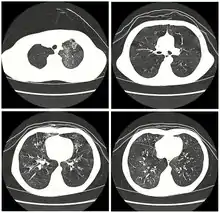

High resolution CT scan showing bronchiolitis obliterans with mosaic attenuation, bronchiectasis, air trapping and bronchial thickening[3] | |

Early in the disease chest radiography is typically normal but may show hyperinflation.[6] As the disease progresses a reticular pattern with thickening of airway walls may be present.[4][6] HRCT can also show air trapping when the person being scanned breathes out completely; it can also show thickening in the airway and haziness in the lungs.[11] A common finding on HRCT is patchy areas of decreased lung density, signifying reduced vascular caliber and air trapping. This pattern is often described as a "mosaic pattern", and may indicate bronchiolitis obliterans.[6]